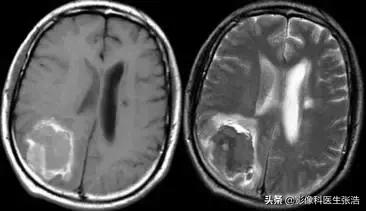

(3)亚急性期:4天至2周内,出血后3-7天为亚急性早期,7-14天为亚急性晚期。

在亚急性早期,去氧血红蛋白被氧化成正铁血红蛋白,它具有5个不成对电子,有很强的顺磁性。脑血肿内正铁血红蛋白首先出现在血肿的周围,并逐渐向血肿内发展。

脑出血亚急性早期

亚急性早期由于正铁血红蛋白形成,T1加权像呈高信号,T2加权像因顺磁性物质的磁敏感效应而呈低信号。

脑出血亚急性晚期

亚急性晚期红细胞开始溶解,在T1或T2加权像上均呈高信号。

红细胞溶解使红细胞对正铁血红蛋白的分隔作用消失,水含量增加是T2加权像信号增高的主要原因。